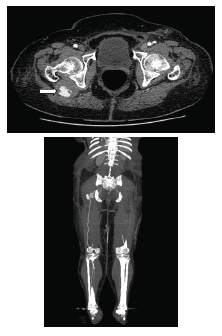

Se consideró que la causa de la isquemia aguda fue la embolia desde el aneurisma de la arteria ciática persistente y que la mayoría del flujo de la extremidad estaba dado por dicha arteria anómala. Con el fin de planear la corrección del aneurisma de la arteria ciática persistente, para evitar eventos isquémicos posteriores, se practicó una angiotomografía de los miembros inferiores (figura 2).